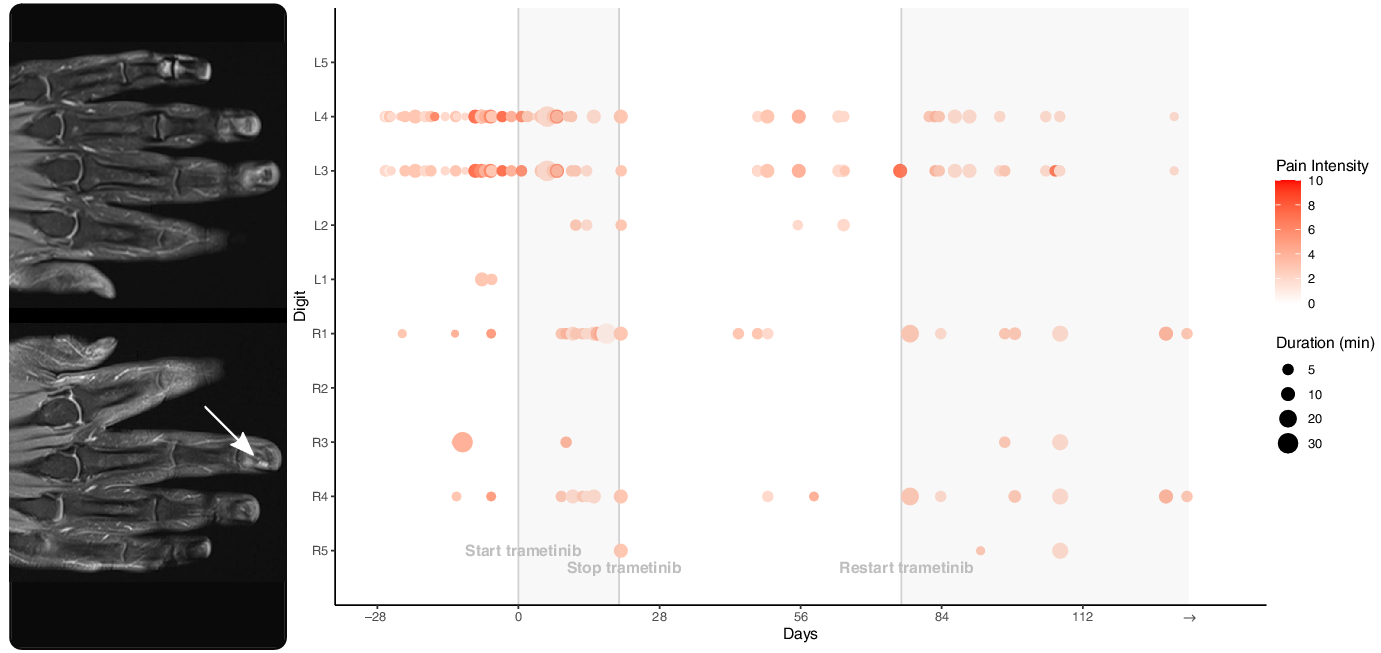

We treated him with trametinib 2 mg orally daily. He recorded his pain crises both before and after starting the drug (Figure 2). In the month leading up to the start of trametinib, he recorded 31 painful episodes, 5 of which were marked as severe (i.e. worse than 5/10). The total time in severe pain that month was 37 minutes. A month after starting trametinib, he recorded 26 painful episodes, 2 of which were marked as severe. He was in severe pain for 15 minutes that month. He developed an acneiform eruption due to trametinib and was started on oral and topical antibiotics. His trametinib was paused and was restarted 8 weeks later at a dose of 0.5 mg daily. His rash is now mild and manageable. A month after restarting trametinib, his painful episodes have reduced in frequency and intensity. He had 12 painful episodes, none of which were marked as severe. A repeat MRI of his hands after 6 months showed stable glomangioma. He continues to take trametinib.

Figure 2: Coronal T1-weighted post-gadolinium MRI of the hands showing small, enhancing glomangiomas, best seen on the right distal 3rd digit (arrow) and on the left 3rd digit (arrow), better seen on axial images. The associated pain scores and durations for each digit are shown in the adjacent graph. The patient recorded his pain crises before and after starting trametinib. Day 0 represents the first day taking trametinib 2 mg daily.